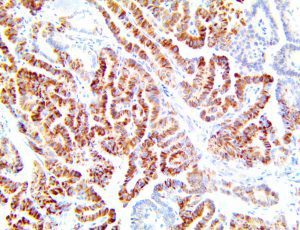

The first cytokines released are interleukin 1β (IL-1β) and tumor necrosis factor-α (TNF-α), which attract a variety of circulating white blood cells (WBCs) to the infection site, including neutrophils, monocytes, macrophages, and natural killer (NK) cells. This response, along with the antipathogenic chemicals released by these cells (i.e., complement), comprise the innate immune response. These cells directly attack the invading pathogen and also release additional cytokines, chief among them interleukin-1 and 6 (IL-6). IL-6 is essential for invoking the adaptive immune response, which calls T-cells, B-cells, and T helper (Th) cells to the infection site. IL-6 also stimulates further recruitment, proliferation and activation of macrophages.

It is the ICU physician who is most likely to witness one of the deadliest manifestations of the abnormal immunological response, the cytokine storm syndrome (CSS). This response is also referred to by some as the cytokine release syndrome (CRS). CSS is characterized by continuous activation and expansion of macrophage and lymphocyte populations, which secrete large amounts of cytokines, causing the cytokine storm. This massive cytokine release is akin to hemophagocytic lymphohistiocytosis (HLH) disease, a syndrome characterized by initial unchecked and persistent activation of cytotoxic T lymphocytes and NK cells.